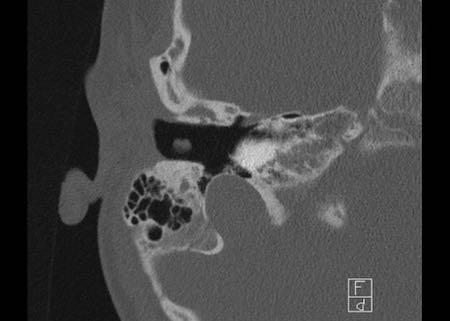

Bên trái là hình ảnh của một bệnh nhân nam 58 tuổi.

Mũi tên màu xanh chỉ cống ốc tai đi về phía ốc tai.

Hình ảnh này có thể bị nhầm lẫn với đường gãy xương (mũi tên).

Lưu ý có hình ảnh mờ đục của hòm nhĩ và các tế bào khí xương chũm.